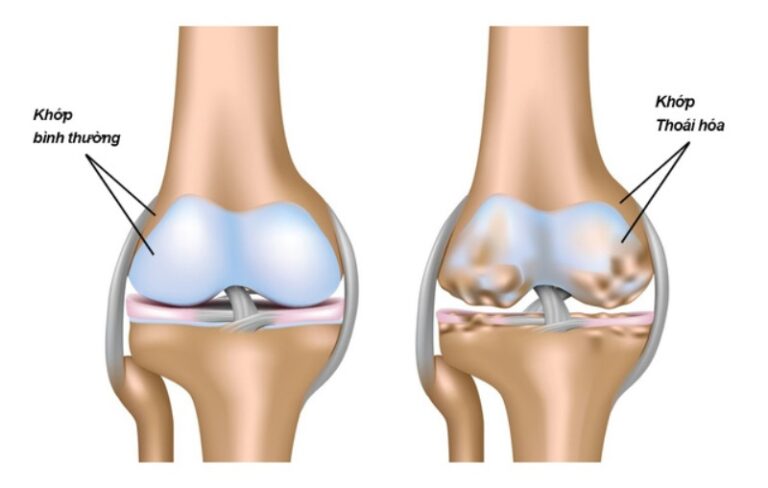

Lớp đệm tại khớp gối bị mài mòn khiến các xương cọ xát trực tiếp với nhau gây đau, cứng khớp

Thoái hóa khớp gối là tình trạng lớp sụn đệm tự nhiên nằm giữa các xương khớp gối bị mài mòn theo thời gian. Sự mài mòn này khiến các đầu xương tại khớp gối cọ xát trực tiếp vào nhau, gây ra cảm giác đau đớn, cứng khớp, và hạn chế nghiêm trọng khả năng vận động. Trong một số trường hợp, bệnh còn dẫn đến sự hình thành của các gai xương ở vùng đầu gối.